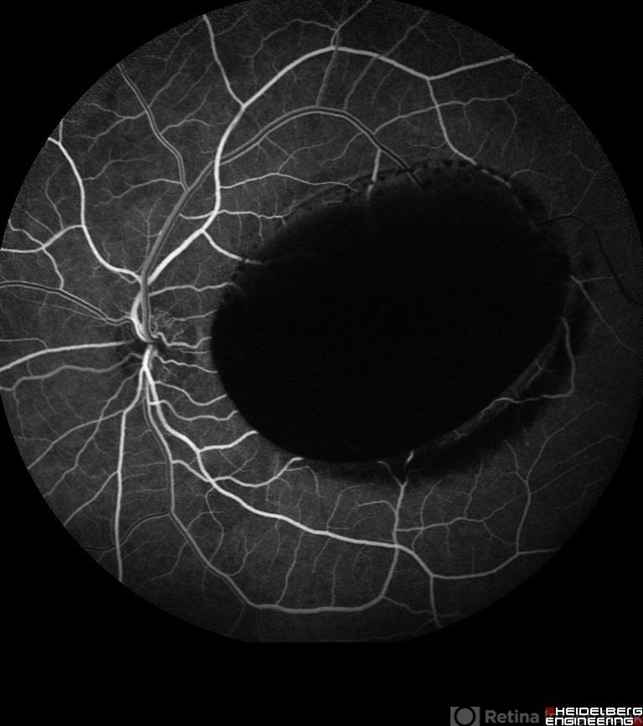

- subhyaloid hemorrhage, valsalva retinopathy

- Nayereh Hadipour, Negah Eye Center, Tehran

- Early venous phase angiogram of the left eye of a 25-year-old man with primary subhyaloid hemorrhage due to Valsalva retinopathy.